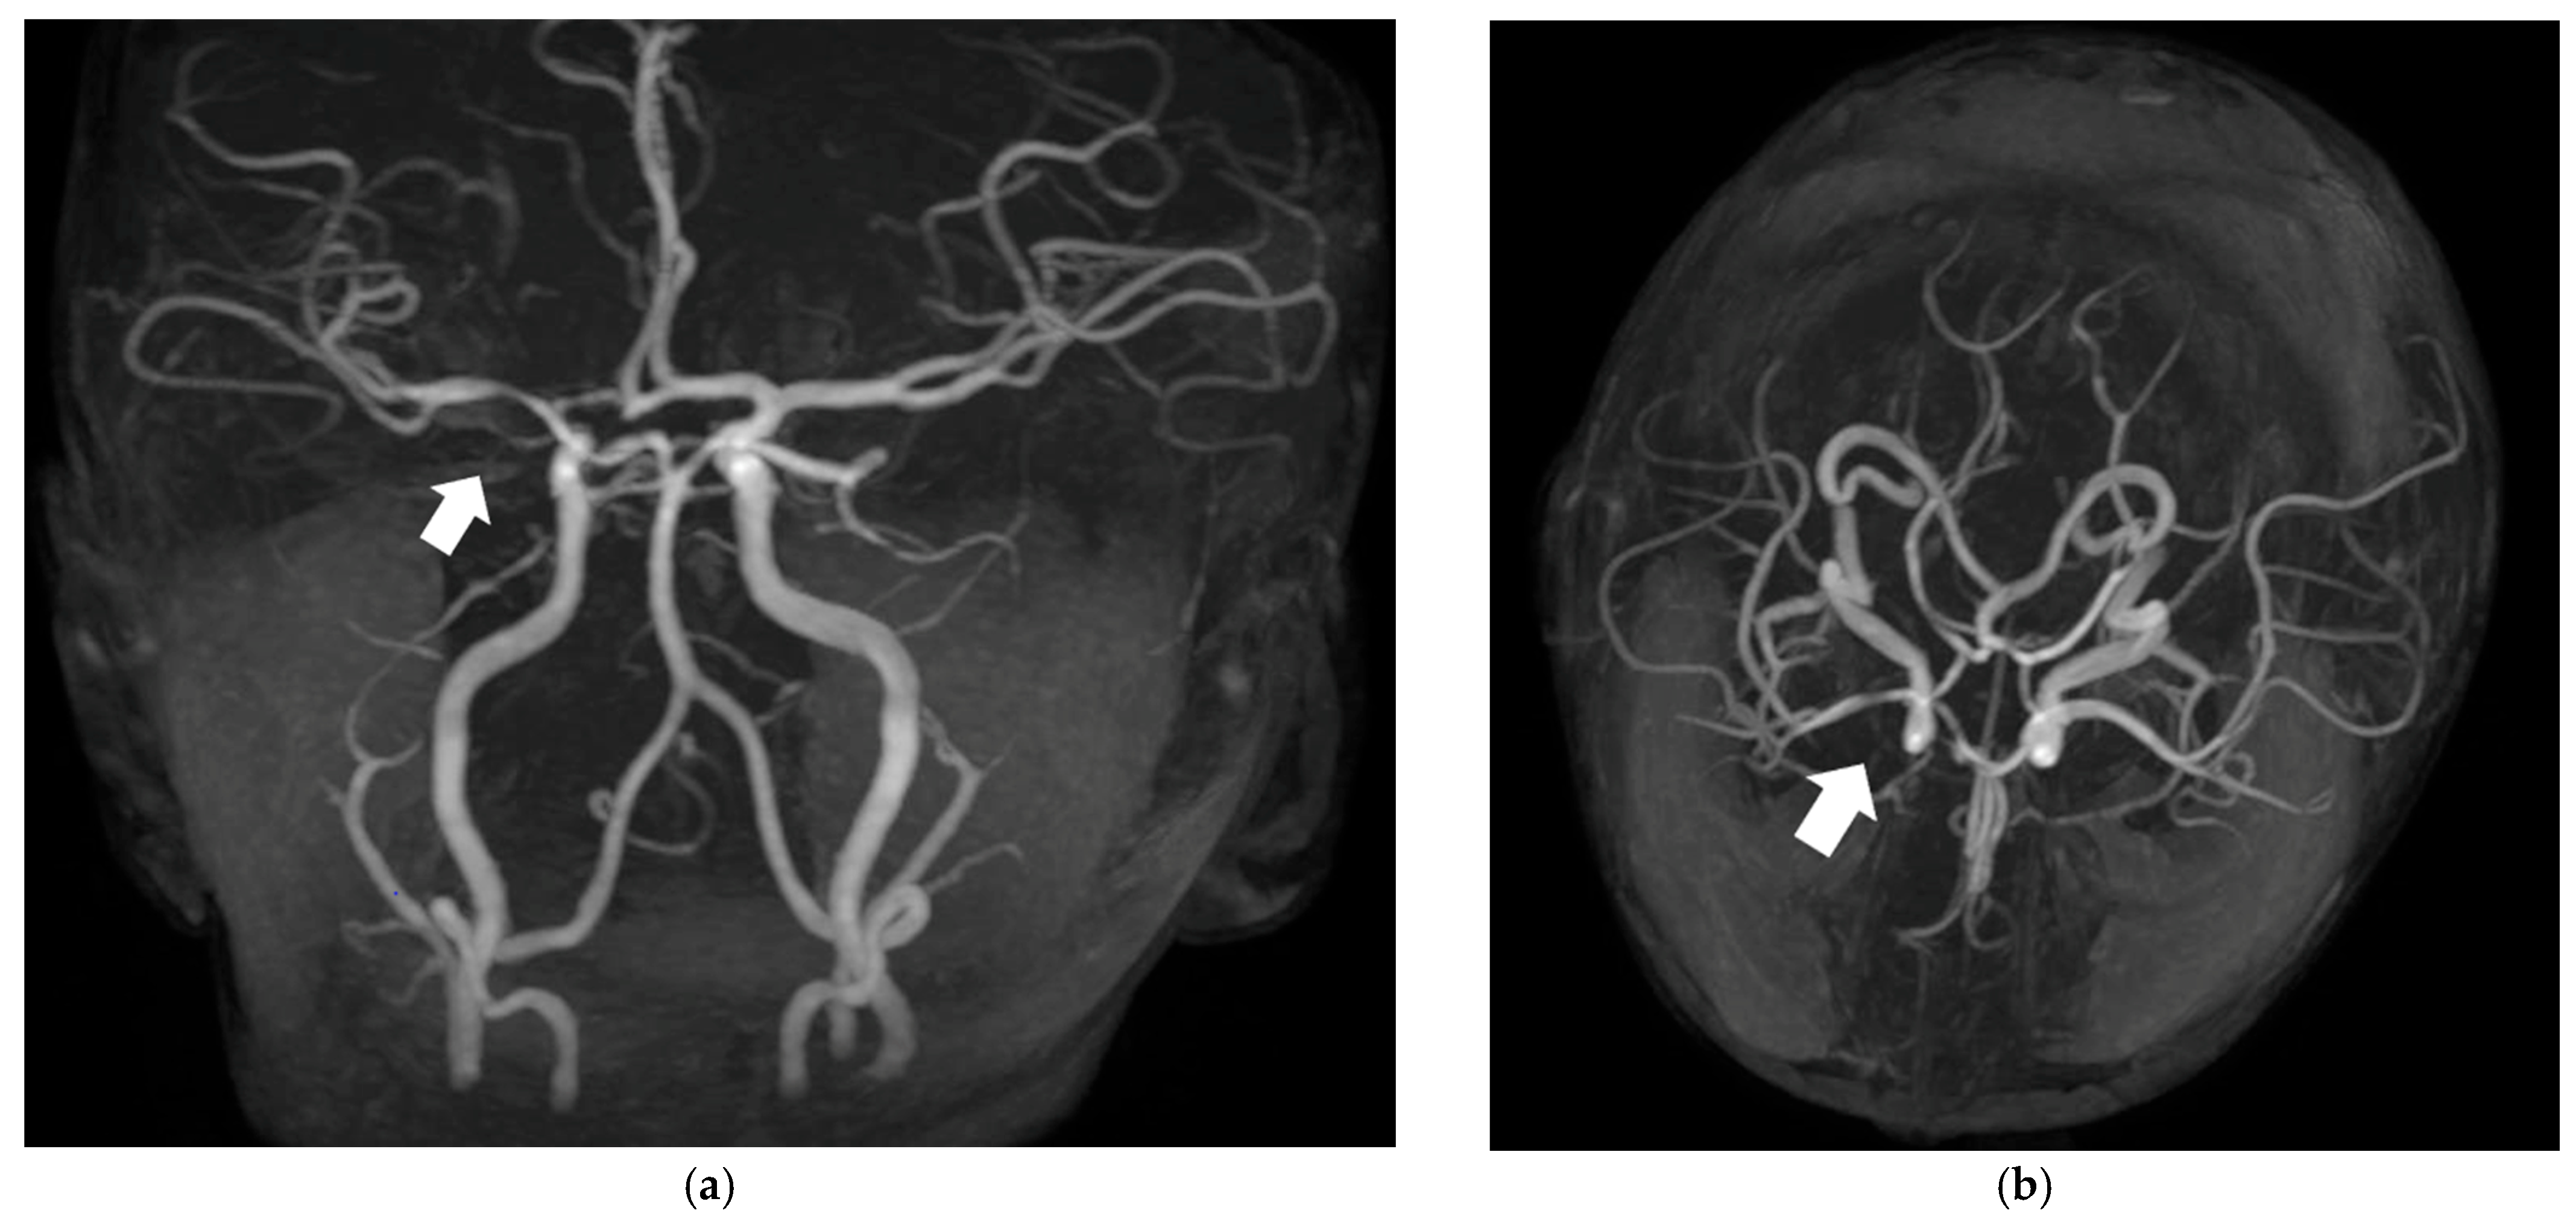

| Our case report | Italy | Case report | 1 | 1 y | 5 mo | Hemiparesis | Unilateral focal stenosis of MCA | Focal cerebral arteriopathy post-VZV, CSF VZV DNA + | Acyclovir + Corticosteroid + ASA | No neurologic residual, no recurrence of AIS |